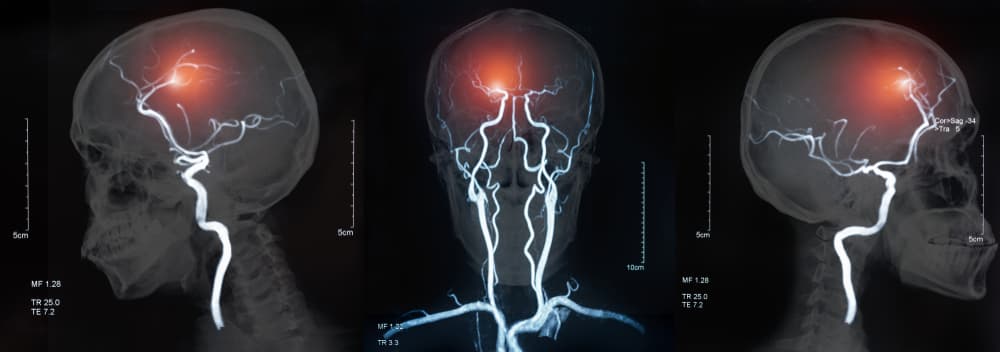

Pero ¿qué es un aneurisma?

Concretamente el aneurisma es el debilitamiento de la pared de una arteria, de acuerdo a Medical News Today. No son peligrosos ni tienen síntomas si se mantienen así, pero si se agrava la situación pueden romperse y generar una hemorragia interna «potencialmente mortal» y puede ocurrir en cualquier parte del cuerpo.

- Aneurisma cerebral